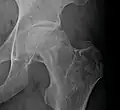

Femoral head showing a flap of cartilage due to avascular necrosis (osteochondritis dissecans). Specimen removed during total hip replacement surgery.